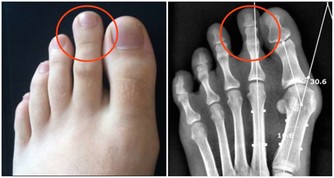

***一是摸腳背,感受足背動脈搏動的強弱。***

通常來說,足背動脈的搏動是對稱的,左腳什麼樣,右腳也什麼樣。除了外傷、風濕免疫疾病等,最常見的造成足背動脈搏動不對稱的原因就是下肢動脈硬化了——硬化、狹窄嚴重的一側,足背動脈會相應變弱。嚴重的,還會出現「走一段路就會腿發沉、腿痛,要休息一會兒才能繼續行走」的情況,這種現像在醫學上被稱為間歇性跛行。